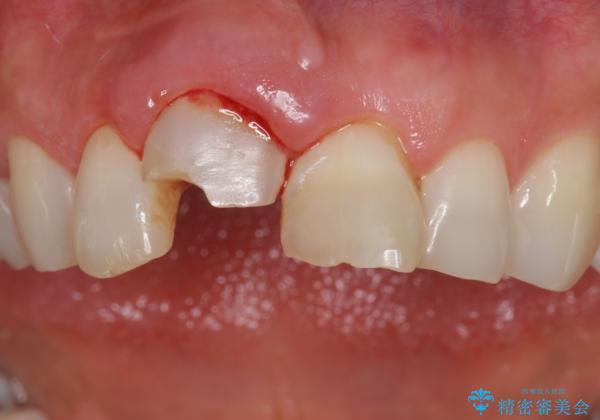

- 転んで前歯が折れたとのことで来院されました。

検査の結果、歯は大きく折れておらず、骨の中に埋め込まれていた状態であったため、部分矯正で歯を引っ張り出していきます。

ぶつけて埋まってしまった歯は、場合によって矯正治療で引っ張り出すことで保存することができます。

今回は歯の神経が死んでしまっていたため、根管治療後に被せ物を装着して見た目の綺麗さを回復しました。

- 右上1/部分矯正:110,000円 根管治療:保険 仮歯:11,000円 ジルコニアクラウン(スペシャル):143,000円費用は治療当時の料金となります